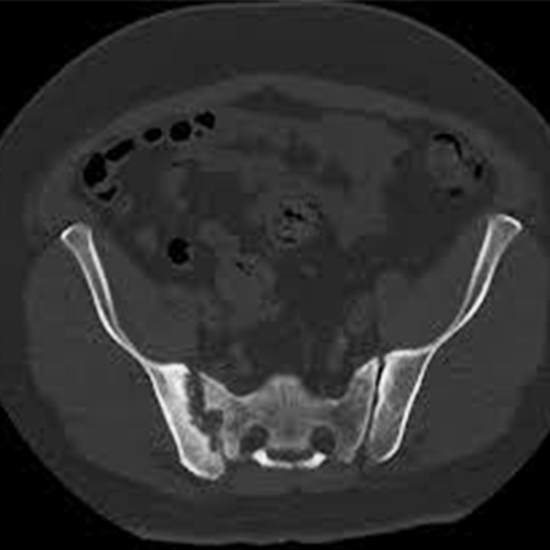

CECT (Contrast Enhanced Computed Tomography) Scan of Bilateral Sacroiliac Joints is an imaging procedure that uses an X-ray beam and involves contrast materials to create a picture of both SI joints and their surrounding tissues.

CECT Scan of Bilateral Sacroiliac Joint is an imaging diagnostic tool using contrast that is used to look for the conditions of the sacral joint and surrounding areas. Patients should not avoid any symptoms related to sacral joint injuries, abnormalities or disorders. Patients should go for screening to avoid any delay in diagnosis and treatment of the sacral joint.